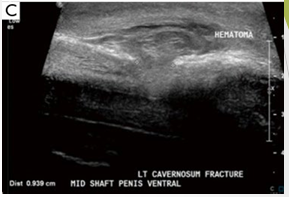

Patient attempting to urinate whilst penis erect. Heard ‘crack’ followed by acute pain

Mid shaft of penis defect noted with disruption of ventral tunica albuginea and left corpus cavernosum. Complex echogenic collection noted along left side of penile shaft

Defect in longitudinal measures 9.4mm. Hematoma noted ventral aspect.